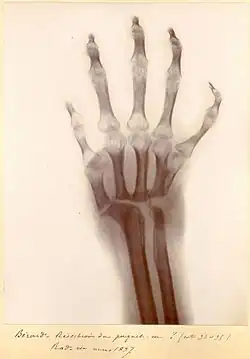

Pour les fractures, il utilise de temps en temps l'ostéosynthèse per cutanée avec une sorte de poinçon ou vrille, des broches, et des fixateurs externes. Certaines radiographies de Destot[6], découvertes par le professeur Fischer, montrent des ostéosynthèses de 1870 à 1900.

![]() |

- Main d'Ollier : main pathologique, caractéristique de la maladie d'Ollier.

- Maladie d'Ollier : maladie congénitale du squelette, nombreux synonymes dont l'enchondromatose.